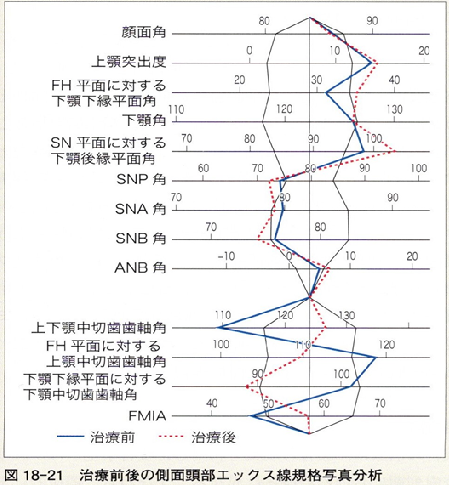

実際の治療でポリゴン表はどのように変化するか?診てみましょう。

第5版 歯科矯正学 図18-21 治療前後の側面頭部エックス線規格写真分析

13項目のうち8項目の数値が悪くなっています。

矯正治療を始めて間もない先生は治療前より治療後がポリゴン表の値は必ず良くなると思っているようですが、そうならない事も多々あります。

それは、矯正学の最終目標が個性正常咬合の確立であって、ポリゴン表の値をそろえる事では無いからです。